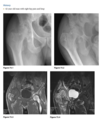

Q

3 x patients with same diagnosis

Anteroposterior view of the pelvis

shows diffuse,

uniform, bony sclerosis and a subtrochanteric frac-

ture of the proximal left femur.

A lateral chest ra-

diograph shows the

sandwich appearance of the vertebral bodies caused

by increased sclerosis of the superior and inferior

end plates.

Radiographs of the knees show splaying of the metaphyses and alternating radiolucent bands in the distal

femurs and proximal tibias and fibulas bilaterally. (Erlenmyer flask)

Diagnosis: Osteopetrosis

Defect in osteoclastic resorption.

Precocious (AR Lethal) and Delayed (AD asymptomatic)

Generalized osteosclerosis and diffuse cortical thick-

ening with narrowing of the medullary cavity.